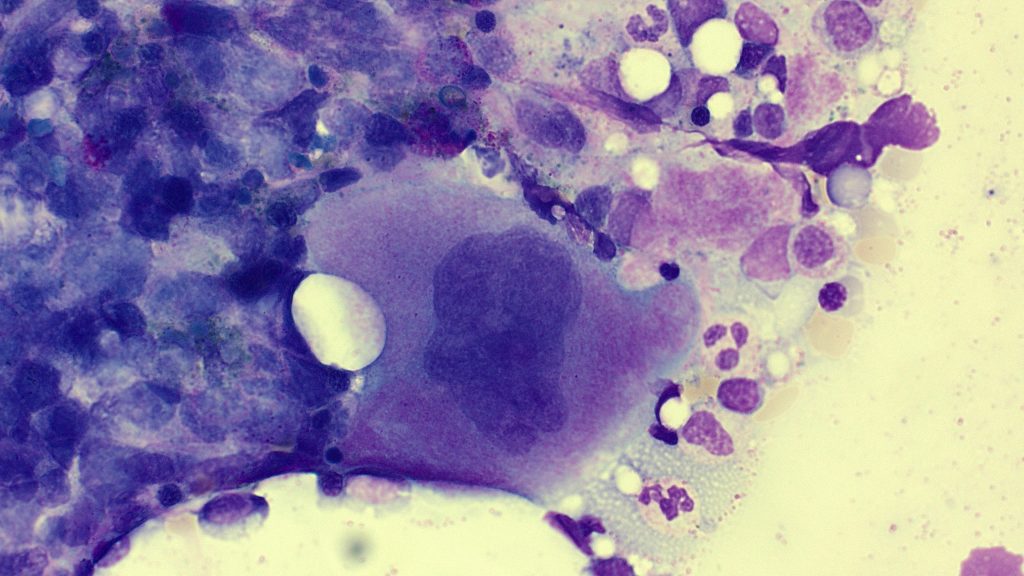

Multiple Myeloma

Dohle bodies

Intranucleolar inclusions

Multiple nuclei

Myeloma Cells